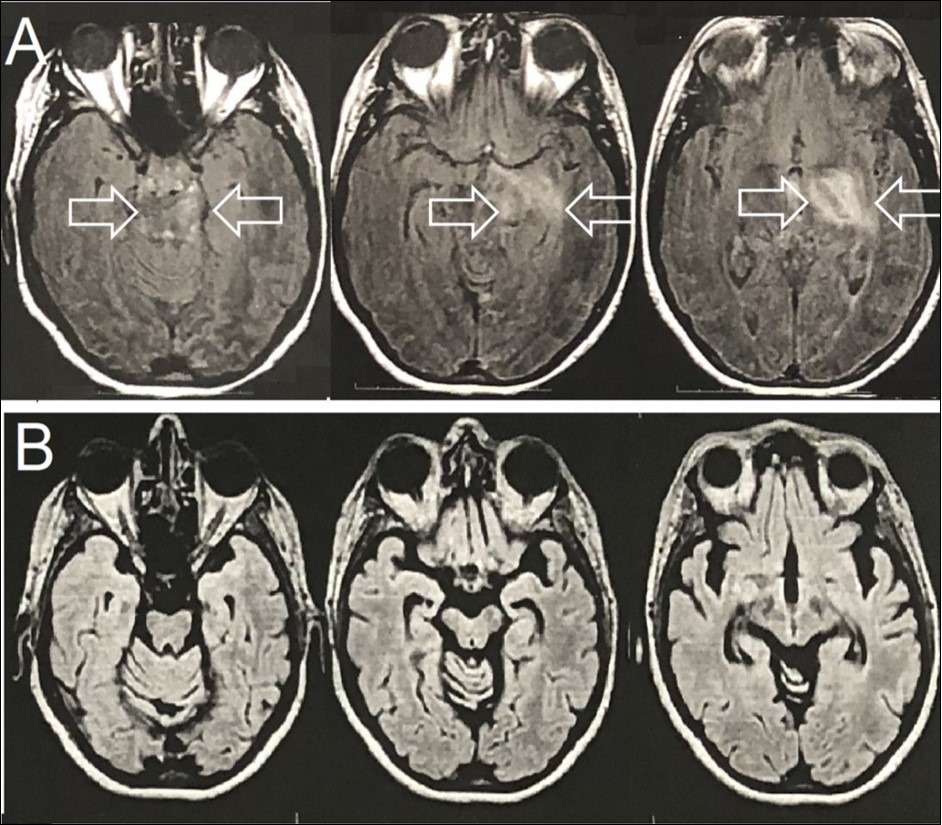

Family medical background was unremarkable. Brain T2-FLAIR magnetic resonance imaging (MRI) showed an expansive mass lesion at the left capsular nucleus region, with mesencephalic extension (Figure 1A). Cerebrospinal fluid analyses showed 15 cells, all of them lympho-monocytes, and protein of 45mg/dL (lumbar puncture). All other tests on spinal fluid were normal.

The patient was also referred to a neurosurgery department, where a brain biopsy was planned for diagnostic clarification. Meanwhile, the possible clinical diagnosis of BD was postulated and started treatment with 1 gram of methylprednisolone intravenously and for a period of 5 days with satisfactory results. Neurosurgery was then discarded. Therapeutic follow-up was instituted with azathioprine and after 2 months of treatment, due to abnormal liver function, anti-TNF-alpha (Infliximab) was was administered at 0, 2nd and 6th weeks and then every eight weeks; Despite cerebral atrophy, stable neurological evolution was found after 18 months of anti-TNF-alpha therapy (Figure 1B).

Figure 1.Brain Axial-FLAIR-MRI- (A) Expansive mass lesion with hyperintense signal in the left capsular nucleus region, with mesencephalic extension and enhancement by the paramagnetic agent (white arrows). (B) Complete improvement of the expansive mass lesion with the presence of brain atrophy.

Neurological involvement occurs in approximately 10% of BD patients and is characterized by an interval of 5 years since the onset of systemic and the neurological symptoms. Clinical and neuroimaging findings suggest parenchymal and extra-parenchymal inflammatory involvement. Pseudotumoral lesion of the Central Nervous System demonstrates inflammatory activity; Brain atrophy can coexist since the beginning of the inflammatory course and demonstrates neurodegeneration. 6 We reported a patient with BD associated with a pseudotumoral lesion of the Central Nervous System, a rare neurological involvement. The patient presented adverse effect to conventional immunosuppressive treatment, with azathioprine and had sustained clinical response with infliximab.